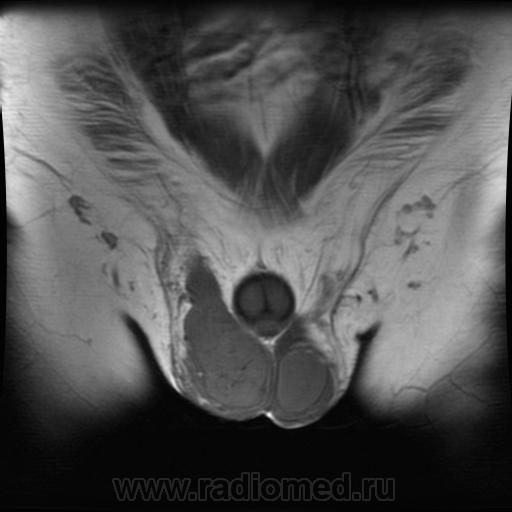

- https://radiomed.ru/sites/default/files/styles/case_slider_image/public/user/1/testis1-t2-sag.jpg?itok=jVH3VBtq

- https://radiomed.ru/sites/default/files/styles/case_slider_image/public/user/1/testis5-t1-cor.jpg?itok=p35KX7Rk

"Мужчина, 60 лет. Около 3 месяцев назад появился дискомфорт в области мошонки, увеличение правого яичка."